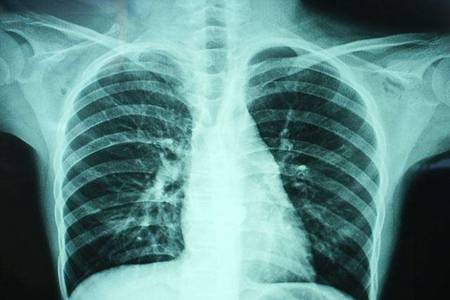

在现代🎯医学的版图中,胸部影像检查(胸片)始终扮演着“前哨兵”的角色。无论是肺部感染、心脏轮廓异常,还是细微的🔥骨骼损伤,胸片都是临床诊断的第一道防线。长期以来,基层医疗机构乃至部分大型医院,都面临着一个难以言说的痛点:影像质量的不稳定性与诊断反馈的滞后性。

在页游网构建的这个技术生态中,软件的🔥优势并📝非孤立存在。当我们谈论“100胸片曝光率”时,我们谈论的是一种对医学严谨性的致敬。高曝光率带📝来的高清晰度,意味着肺纹理的走向、纵隔的微小位移甚至是早期结节的蛛丝马迹,都能在屏幕上纤毫毕现。这种视觉上的🔥进化,直接降低了放射科医生的阅片难度,将以往需要依靠经验“猜测”的部分,转化为清晰可见的数据证据。

技术的终极目的永远是服务于“人”。在医疗场景中,时间就是生命,而精准则是生命的底色。这款软件在提升曝光精准度的极大地缩短了二次采🔥像的概率。在过去,如果由于曝光问题导致片子质量不合格,患者需要重新接受放射照射,这不仅增加了患者的辐射摄入,更拉长了整个就医周期。